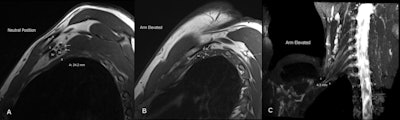

Neurovascular compressions are often not demonstrated in the neutral position, highlighting the necessity for dynamic MRI. In contrast, the scalene triangle and rectopectoralis minor space demonstrate an equal or lesser degree of compression in thoracic outlet syndrome patients compared to asymptomatic patients.

At the Princess Alexandra Hospital, imaging is performed on a 3-tesla scanner with sequences consisting of 3D SPACE [sampling perfection with application-optimized contrasts using a different flip angle evolution] STIR [short tau inversion recovery] images in a coronal plane orientated to the neurovascular bundle, sagittal Dixon T2 images, and T-weighted images with the imaged volume extending through the supraclavicular fossa to the humerus.

Sequences are performed with the arm in both neutral position and in abduction with external rotation. Additionally, a sagittal T2 cervical spine is performed to assess cervical nerve roots.